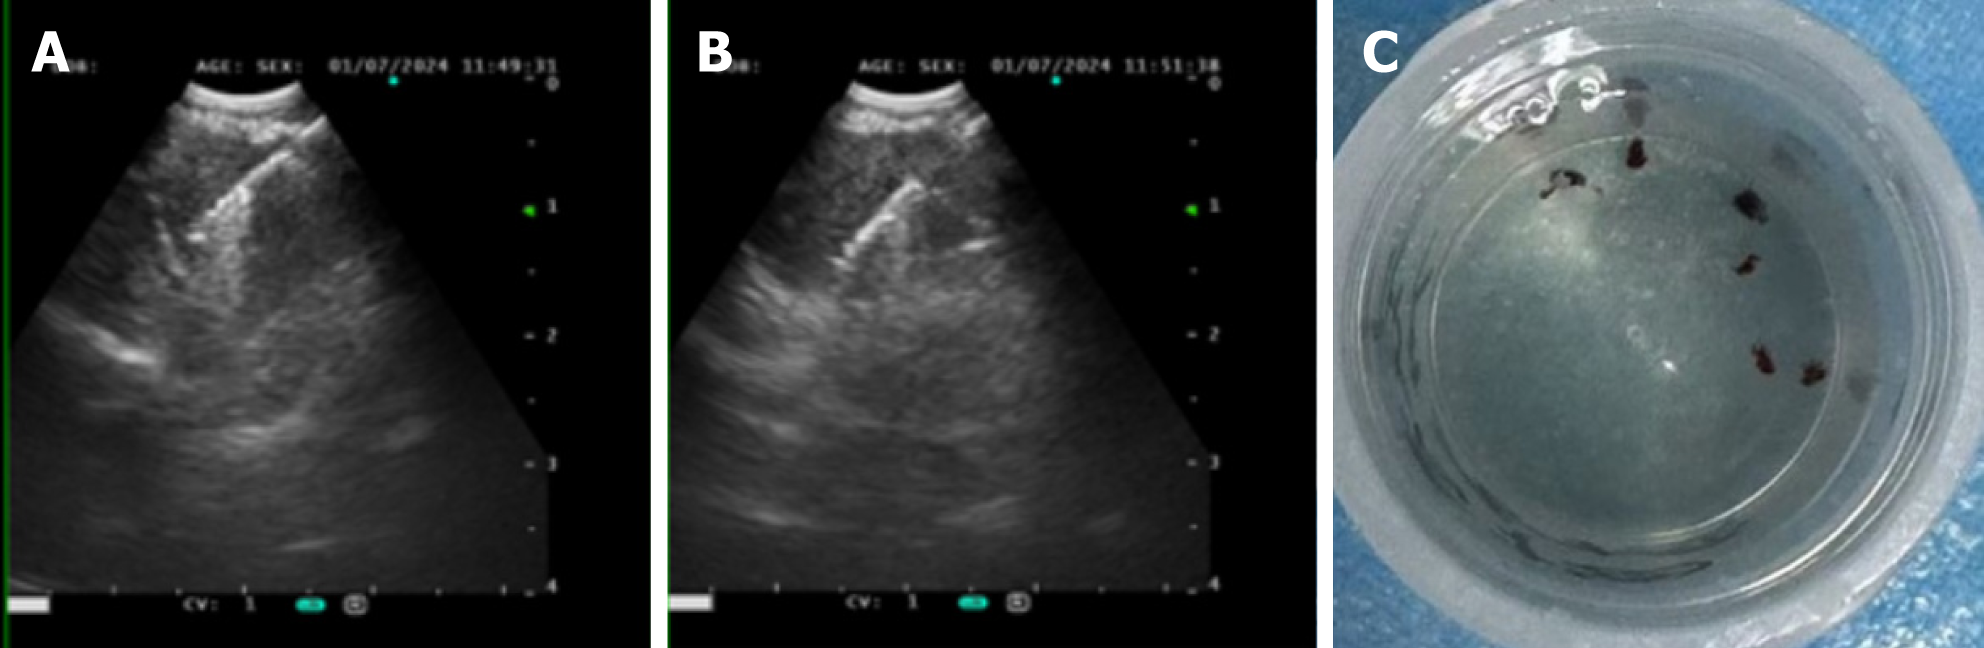

Case 1: Bronchoscopic lavage (June 7, 2024) showed no tumor cells. There were no remarkable results in initial diagnostic evaluations, including routine blood tests, erythrocyte sedimentation rate, biochemistry, coagulation profile, cardiac markers, and serum tumor markers. A repeat procedure was performed on July 1, 2024, under informed consent due to inconclusive findings from the previous bronchoscopy. Bronchoalveolar lavage fluid analysis showed no pathogens but a lymphocyte count of 12002/μL and a CD4/CD8 ratio of 5.81. A biopsy of the right upper lobe apical segment lesion was obtained, followed by EBUS-TBNA using an Olympus 21-G needle to sample station 7 Lymph nodes and posterior upper tracheal soft tissue (Figure 1). Subsequently, EBUS-TBFB was conducted by inserting a 1.2-mm fine biopsy forceps through the pre-established 21-G puncture site under real-time ultrasound guidance. As a result, 4-6 mediastinal biopsies with specimens ≥ 3 mm in diameter were obtained. No post-procedural bleeding was observed. There were scattered epithelial cells, inflammatory infiltrates, and multinucleated giant cells, but no atypia or granulomas in the histopathological analysis of EBUS-TBNA specimens, whereas EBUS-TBFB samples confirmed non-caseating granulomas with multinucleated giant cells (Figure 2A). Immunohistochemistry demonstrated Cytokeratin pan (epithelial+), CD68 (KP-1+), S-100 (−), and Ki-67 (high expression in inflammatory cells), while special stains for acid-fast bacilli, periodic acid-schiff, and Gomori methenamine silver were negative. Serum angiotensin-converting enzyme levels were elevated at 76.3 U/L.

Case 2: Initial diagnostic evaluations revealed thrombocytopenia (55 × 109/L) with normal coagulation parameters, biochemistry, tumor markers, and negative antinuclear antibodies. Pulmonary function tests indicated mild obstructive ventilatory impairment, while a nasopharyngeal biopsy demonstrated lymphoid hyperplasia. There was no remarkable abnormal phenomenon in fundoscopic examination, and a bone marrow biopsy performed on December 17, 2024, showed partial megakaryocyte maturation arrest without atypia or fibrosis. On December 19, 2024, bronchoscopy with bronchoalveolar lavage fluid analysis revealed a CD4/CD8 ratio of 4.68 under general anesthesia. Concurrently, EBUS-TBNA using an Olympus 21-G needle (three passes) and EBUS-TBFB were performed on subcarinal (station 7) lymph nodes via the same puncture site, adhering to the protocol described in Case 1. The EBUS-TBFB yielded specimens with a diameter of at least 3 mm. In accordance with the histopathological examination, non-caseating granulomas without necrosis were identified (Figure 2B and C), and serum angiotensin-converting enzyme levels were elevated at 51.1 U/L.